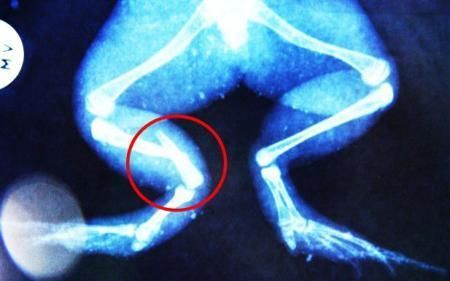

環(huán)球網(wǎng)4月2日報(bào)道 據(jù)《每日郵報(bào)》報(bào)道,上個(gè)月,南非大牛蛙布魯萊的右小腿被鄰居家的一只狗咬到,導(dǎo)致粉碎性骨折,現(xiàn)在經(jīng)過2個(gè)小時(shí)的手術(shù),它的斷腿已經(jīng)被接上,它也因此成為有史以來第一只通過外科手術(shù)用鋼針接上斷腿的青蛙。

布魯萊的主人,居住在南非約翰內(nèi)斯堡附近的62歲的安妮·米恩斯說:“我對這只青蛙如此關(guān)心,人們一定認(rèn)為我瘋了,但是我無法眼睜睜看著它那么痛苦。青蛙因其靈活的腿腳而著稱,一想到布魯萊的腿里要留下一個(gè)薄金屬片,我就感到心痛。然而我知道,如果不進(jìn)行手術(shù),布魯萊以后就沒辦法動(dòng)彈了。因此我匆匆趕到獸醫(yī)那里,央求他給這只可憐的青蛙動(dòng)手術(shù)。這位獸醫(yī)整天救助小貓小狗,他很難理解為什么我這么擔(dān)心一只青蛙,但是最終他還是答應(yīng)了給布魯萊做手術(shù)。手術(shù)后是幾個(gè)小時(shí)的焦急等待,我們希望它能快快蘇醒過來。不過現(xiàn)在它的傷口已經(jīng)愈合,又能在花園里跳來跳去了。X光照射顯示,它會(huì)恢復(fù)的跟以前一樣!

野生生物專家安妮經(jīng)常為學(xué)校寫教材,她認(rèn)為這是人類第一次通過手術(shù)給一只青蛙接斷腿。在手術(shù)開始階段,獸醫(yī)把少量給狗用的麻醉藥注入到這只青蛙體內(nèi),讓它失去知覺。然后他在布魯萊的斷腿上切開一個(gè)小口,把一根小鋼針植入腿里。最后獸醫(yī)給它縫了9針,把切口縫合在一起。僅僅幾周后,布魯萊就能在安妮家附近活動(dòng)了。這只青蛙大約已有25歲,主要以嚙齒動(dòng)物、蛇和其他青蛙為食。布魯萊所屬的牛蛙種群正在不斷減小,目前只能在非洲南部的濕地里才能看到這種青蛙。